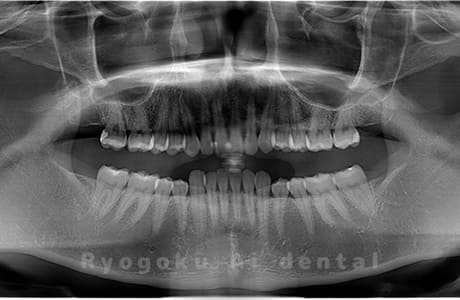

Case05

-

- 原因

- 下顎の親知らず2本

- 治療内容

- 下顎の親知らず2本を抜歯したケースです。

<リスク・副作用>

手術後は痛み、腫れ、痺れなどの副作用が生じる場合があります。